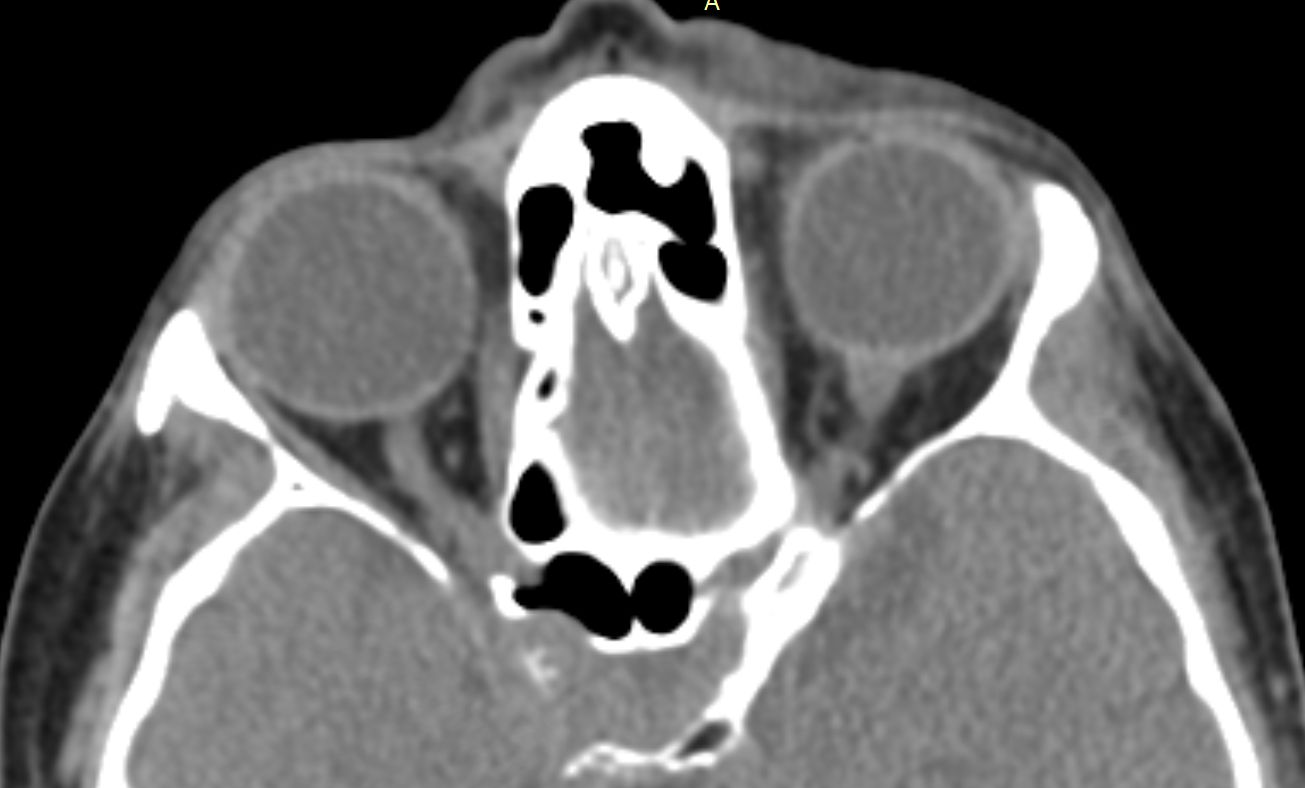

КТ-снимки хронического этмоидита: подробная визуализация

Раздел: Фотодневник открытий